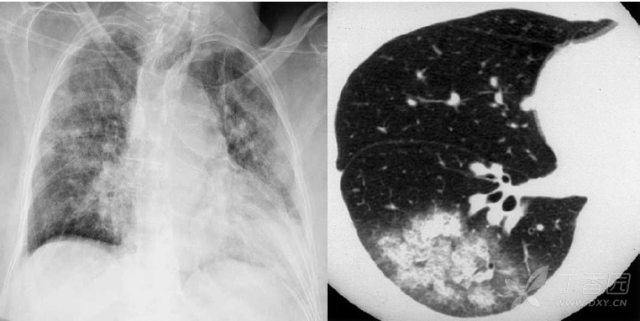

胸部ct 入门 这6 种征象最常见 丁香园